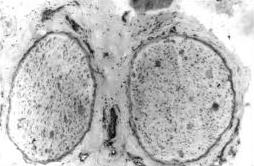

Distrofia neuroaxonal infantil se caracteriza por el desarrollo de inflamaciones llamados cuerpos esferoidales en los axones, las fibras que se extienden desde las células nerviosas y transmiten impulsos a los músculos y otras neuronas. Una parte del cerebro llamada el cerebelo, que ayuda a controlar los movimientos, también puede ser dañado. En algunas personas con distrofia neuroaxonal infantil, cantidades anormales de hierro se acumulan en una región específica del cerebro llamada ganglios basales.

Las mutaciones en el gen PLA2G6 se han identificado en la mayoría de los individuos con distrofia neuroaxonal infantil. El gen PLA2G6 proporciona instrucciones para hacer una enzima llamada fosfolipasa A2. Esta familia de la enzima está implicada en el metabolismo de los fosfolípidos. Metabolismo de los fosfolípidos es importante para muchos procesos corporales, incluyendo ayudando a mantener la membrana celular intacta y funcionando correctamente. Específicamente, la fosfolipasa A2 produce a partir del gen PLA2G6, a veces llamado PLA2 grupo VI, ayuda a regular los niveles de un compuesto llamado fosfatidilcolina, que es abundante en la membrana celular. Las mutaciones en el gen PLA2G6 perjudican la función de la enzima PLA2 grupo VI. Este deterioro de la función de la enzima puede alterar mantenimiento de la membrana celular y contribuir al desarrollo de los cuerpos esferoidales en los axones de los nervios. Aunque no se sabe cómo los cambios en la función principal de esta enzima a los signos y síntomas de la distrofia neuroaxonal infantil, problemas de metabolismo de fosfolípidos se han visto tanto en este trastorno y un trastorno relacionado llamado pantotenato quinasa asociada a la neurodegeneración. Estos trastornos, así como la enfermedad de Alzheimer más común y la enfermedad de Parkinson, también se asocian con cambios en el metabolismo cerebral de hierro. Los investigadores están estudiando los vínculos entre los defectos de fosfolípidos, hierro cerebral y daños a las células nerviosas, pero no han determinado cómo la acumulación de hierro que se produce en algunas personas con distrofia neuroaxonal infantil puede contribuir a las características de este trastorno. No se han encontrado unos individuos con distrofia neuroaxonal infantil de tener mutaciones en el gen PLA2G6. La causa genética de la enfermedad en estos casos es desconocida; existe evidencia de que al menos otro gen puede estar implicado. Las mutaciones en el gen NAGA, lo que resulta en la deficiencia de alfa-N-acetilgalactosaminidasa, causan una distrofia neuroaxonal infantil conocida como enfermedad de Schindler.